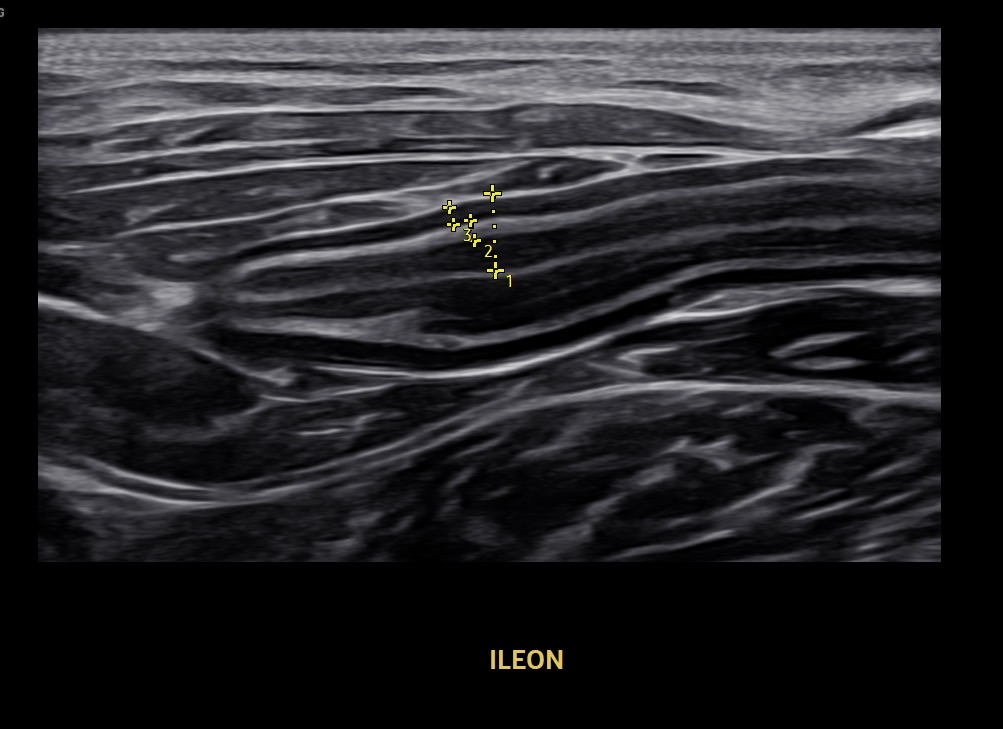

Ecografía digestiva felina

Un tutorial para optimizar tus habilidades en ecografía